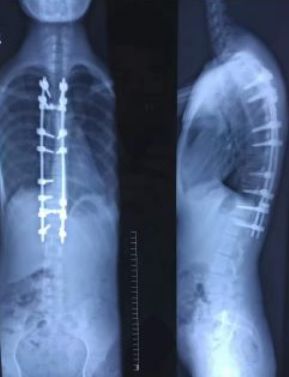

平时大家自己在拍照的时候,可以随意的摆姿势、做造型、带装饰物。因为放射性的检查是一种对人体有危害的检查手段,所以在做放射检查的时候一般会尽可能的显示病变的同时减少检查次数,一般主要会在正位、侧位、斜位中选择体位。姿势就不能任大家随意摆。